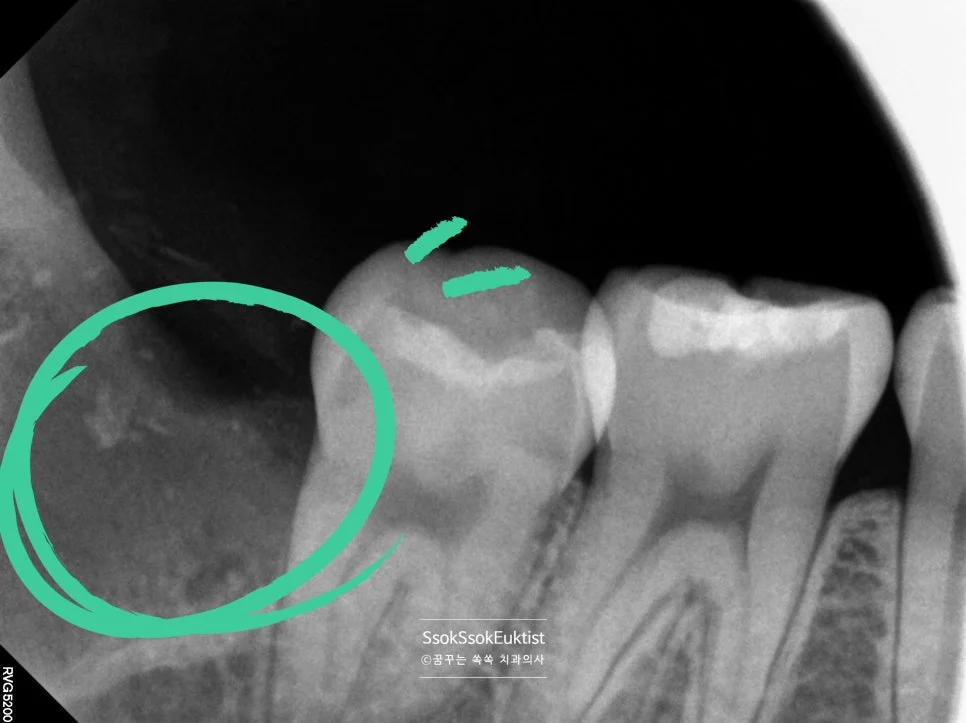

신경관 근접 매복 사랑니 엑스레이

잔존 뿌리 없이 발치가 아주 잘 된 모습이고요^^

어려운 난이도 — 완전히 누워 있는 수평 매복 사랑니

X-ray 사진을 보면 사랑니가 완전히 누워 있어 사랑니를 빼기 위해서는 깊숙한 곳까지 도달하여 치아를 분리해야 할 것 같은데요~^^

CBCT 3차원 영상 — 서로 다른 방향으로 휘어진 복잡한 뿌리

3차원 사진을 통해 보면 뿌리가 서로 다른 방향으로 휘어 있어 뼈를 잡고 있는 모습인데요^^ 이런 뿌리의 사랑니의 경우 한꺼번에 나오지 않으므로 머리를 분리하는 것 외에 뿌리도 분리하여 사랑니를 제거해야 합니다.